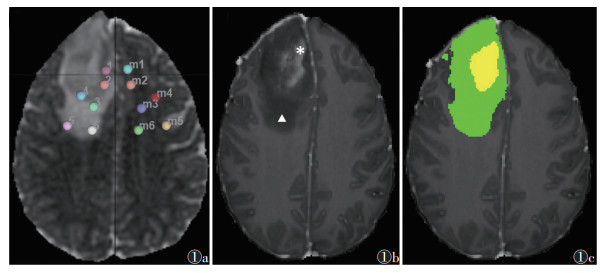

DTI参数测量使用DSI studio(版本2024.1.9,https://dsi-studio.labsolver.org/)软件,参数包括FA值、平均扩散率(mean diffusivity,MD)、轴向扩散率(axial diffusivity,AD)和径向扩散率(radial diffusivity,RD)。由2位分别具有5、6年工作经验的医师在不知道病理结果的情况下独立勾画圆形ROI,直径5 mm(图 1a),并在瘤体强化区域、瘤周水肿近侧、瘤周水肿远侧分别测量2次DTI参数取平均值并记录;在瘤体侧ROI对称的脑实质区域手动勾画ROI,将肿瘤侧DTI参数除以对侧DTI参数得到FA、MD、AD和RD相对值(rFA、rMD、rAD、rRD)[12]。脑肿瘤存在占位效应、无法直接进行镜像操作或对称位置为脑室或脑沟时,可在邻近位置或层面勾画ROI。

| 注:图1a为测量DTI参数时的ROI放置,ROI 1~2、3~4、5~6分别放置在肿瘤强化区域、不强化/瘤周水肿的近侧及远侧区域,ROI m1~m6分别表示镜像对侧大脑半球区域的ROI放置;图1b为T1WI增强扫描图像,可见肿瘤强化区域呈高信号(*),瘤周水肿不强化呈低信号(▲);图1c显示数据集自带的分割图像上分别对应黄色区域和绿色区域,可使ROI准确放置 图 1 ROI勾画示意图 |

肿瘤体积采用ITK-SNAP(版本3.8,http://www.itksnap.org/)软件。通过软件自带肿瘤分割数据(图 1b,1c),直接获取强化体积、坏死体积、水肿体积,并计算肿瘤体积(肿瘤体积=强化体积+坏死体积)、体积比(强化/瘤体、水肿/瘤体、坏死/瘤体及强化/水肿)。